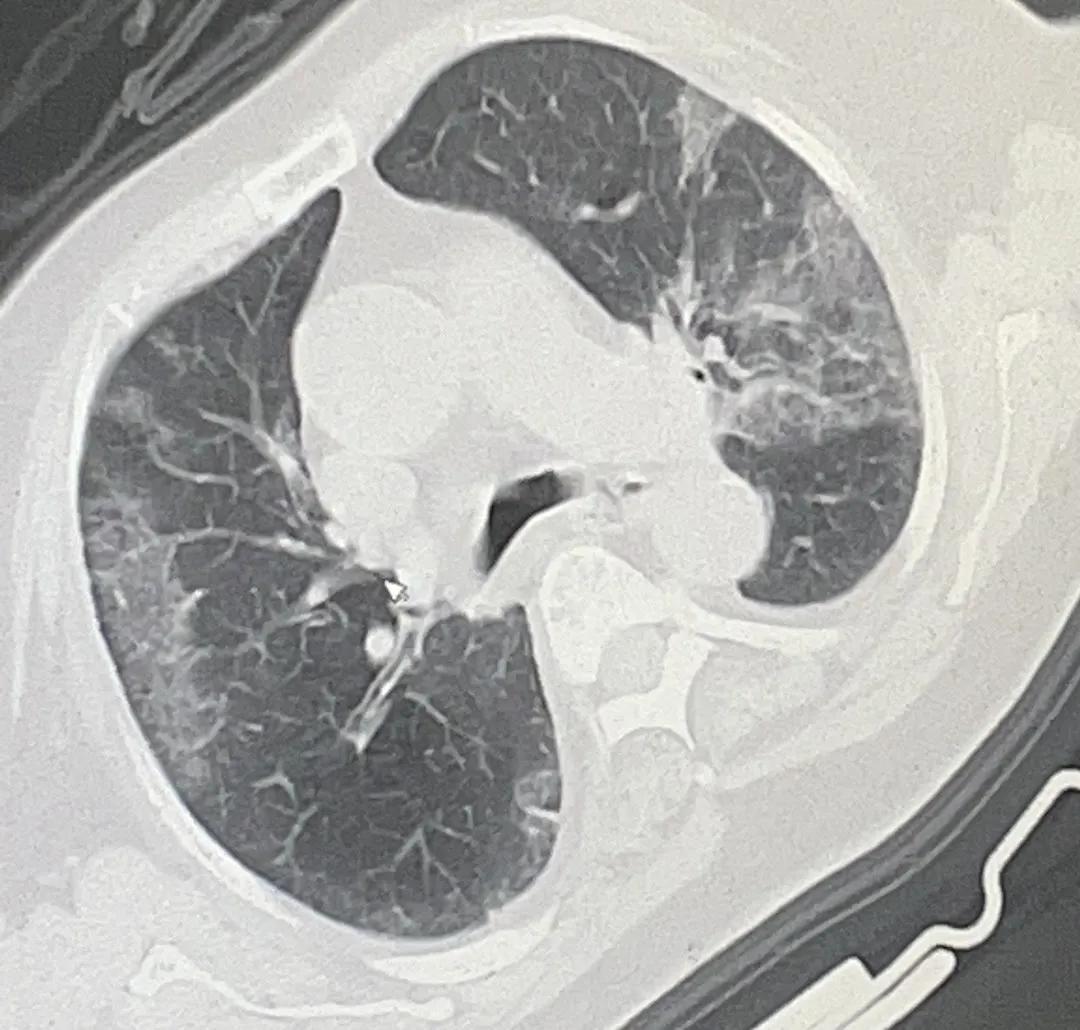

姥姥肺部影像(部分)

可以看到,姥姥双肺已经出现大面积的白色块状物,看到肺部影像,医生建议:病情恶化,立即住院。